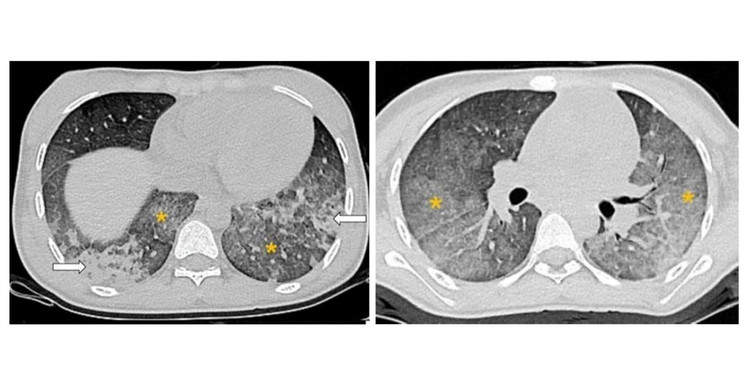

Chụp cắt lớp vi tính lồng ngực cho thấy hình ảnh các tổn thương gợi ý chảy máu phế nang lan tỏa.

X-quang ngực có tổn thương mờ thâm nhiễm cả hai phổi, CT có hình kính mờ lan tỏa, đông đặc, dày vách phế nang phù hợp với hình ảnh của chảy máu phế nang lan tỏa.